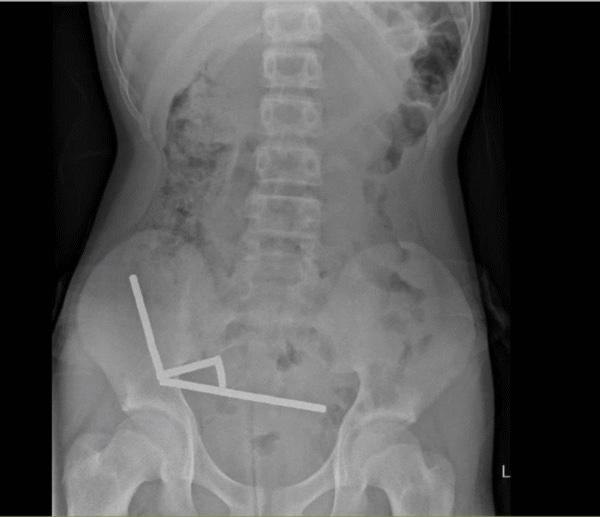

X光中顯示,這些小磁鐵在他腸子裡的不同部位中形成4條鏈子互相拉扯,並切斷了附近組織的血流,壓力更導致多處壞死。

醫生為他移除磁鐵和部分受損腸道,男童最終在醫院裡住了8天。